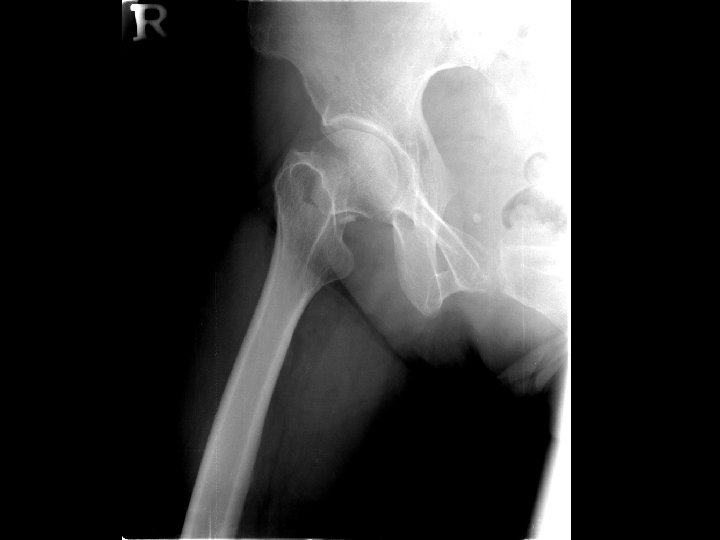

Patient profile n n Name:游 XX 菊 Gender: Female Age: 59 years old Chart number: 02766663

Chief complaint n Right hip painful deformity

Present illness n n The 59 year-old female was a victim of hypertension before. On 95. 3. 7, she suffered from slipped down and felt right hip pain and can’t walk. She was brought to our OPD for help. Severe pain with limited ROM was noted.

Physical examination n n Tenderness, swelling of the right hip ROM limitation (+), severe pain when moving

Tentative diagnosis n Right femoral neck fracture, Garden type III